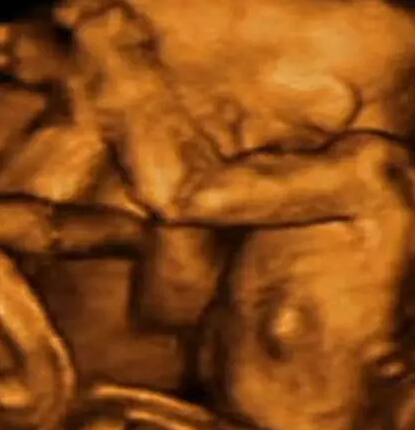

研究中运用了4-D扫描图像,这些图像通过真实拍摄的3-D扫描图像合成。

4-D扫描图显示了双胞胎在子宫中活动的情况。胎儿为了争夺生存空间和养料而彼此推挤。

科学家通过计算机生成图像获取了双胞胎、三胞胎和四胞胎如何在子宫中发育的新信息。